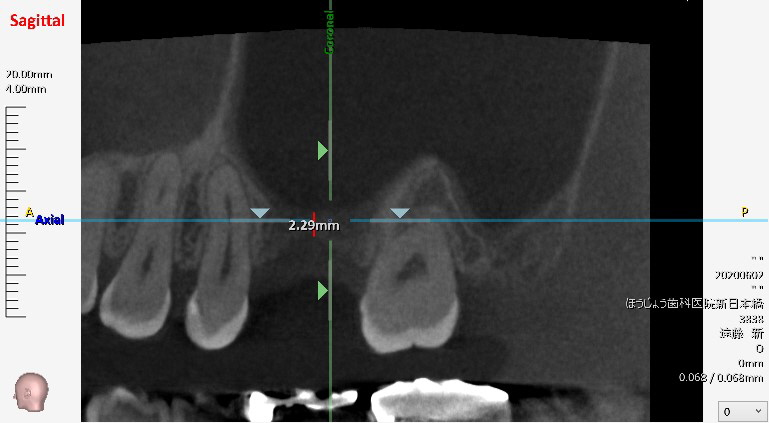

このような骨が薄い症例はインプラントを通法通りに埋入することが出来ません。

現在、日本で使用可能なインプラントは6mm以上の長さになります。

このような症例では、サイナスリフトという、上顎洞を挙上する処置を併用しなければなりません。